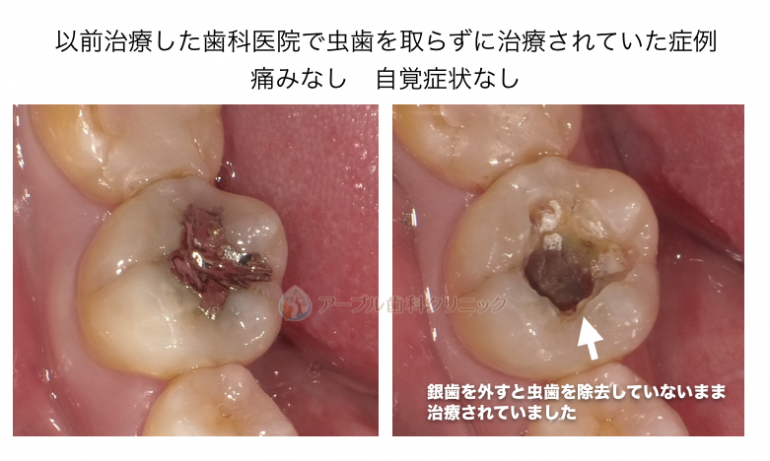

以前治療した銀歯の内部から虫歯の取り残しが見つかった症例

銀歯の内部で虫歯の取り残しがあった症例